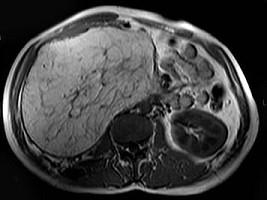

问题 男,30岁。右侧腹部包块渐增大,伴胀痛1年余。MRI检查见巨大包块,最可能的诊断是 ( )

选项 A、右肾巨大血管瘤 B、右肾错构瘤 C、右肾髓样脂肪瘤 D、右肾畸胎瘤 E、右侧肾上腺腺瘤

答案 C